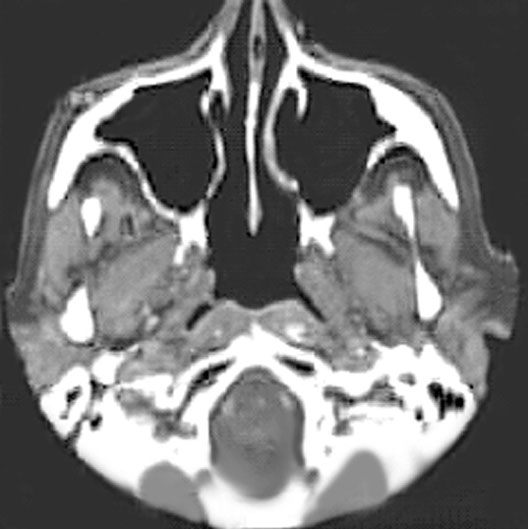

Head CT

1. Maxillary sinus

2. Cartilage part of nasal septum

3. Bony part of nasal septum

4. Auditory tube